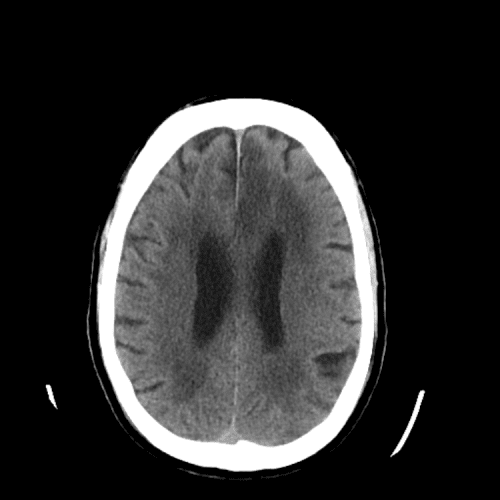

PICA infarct

Case #4